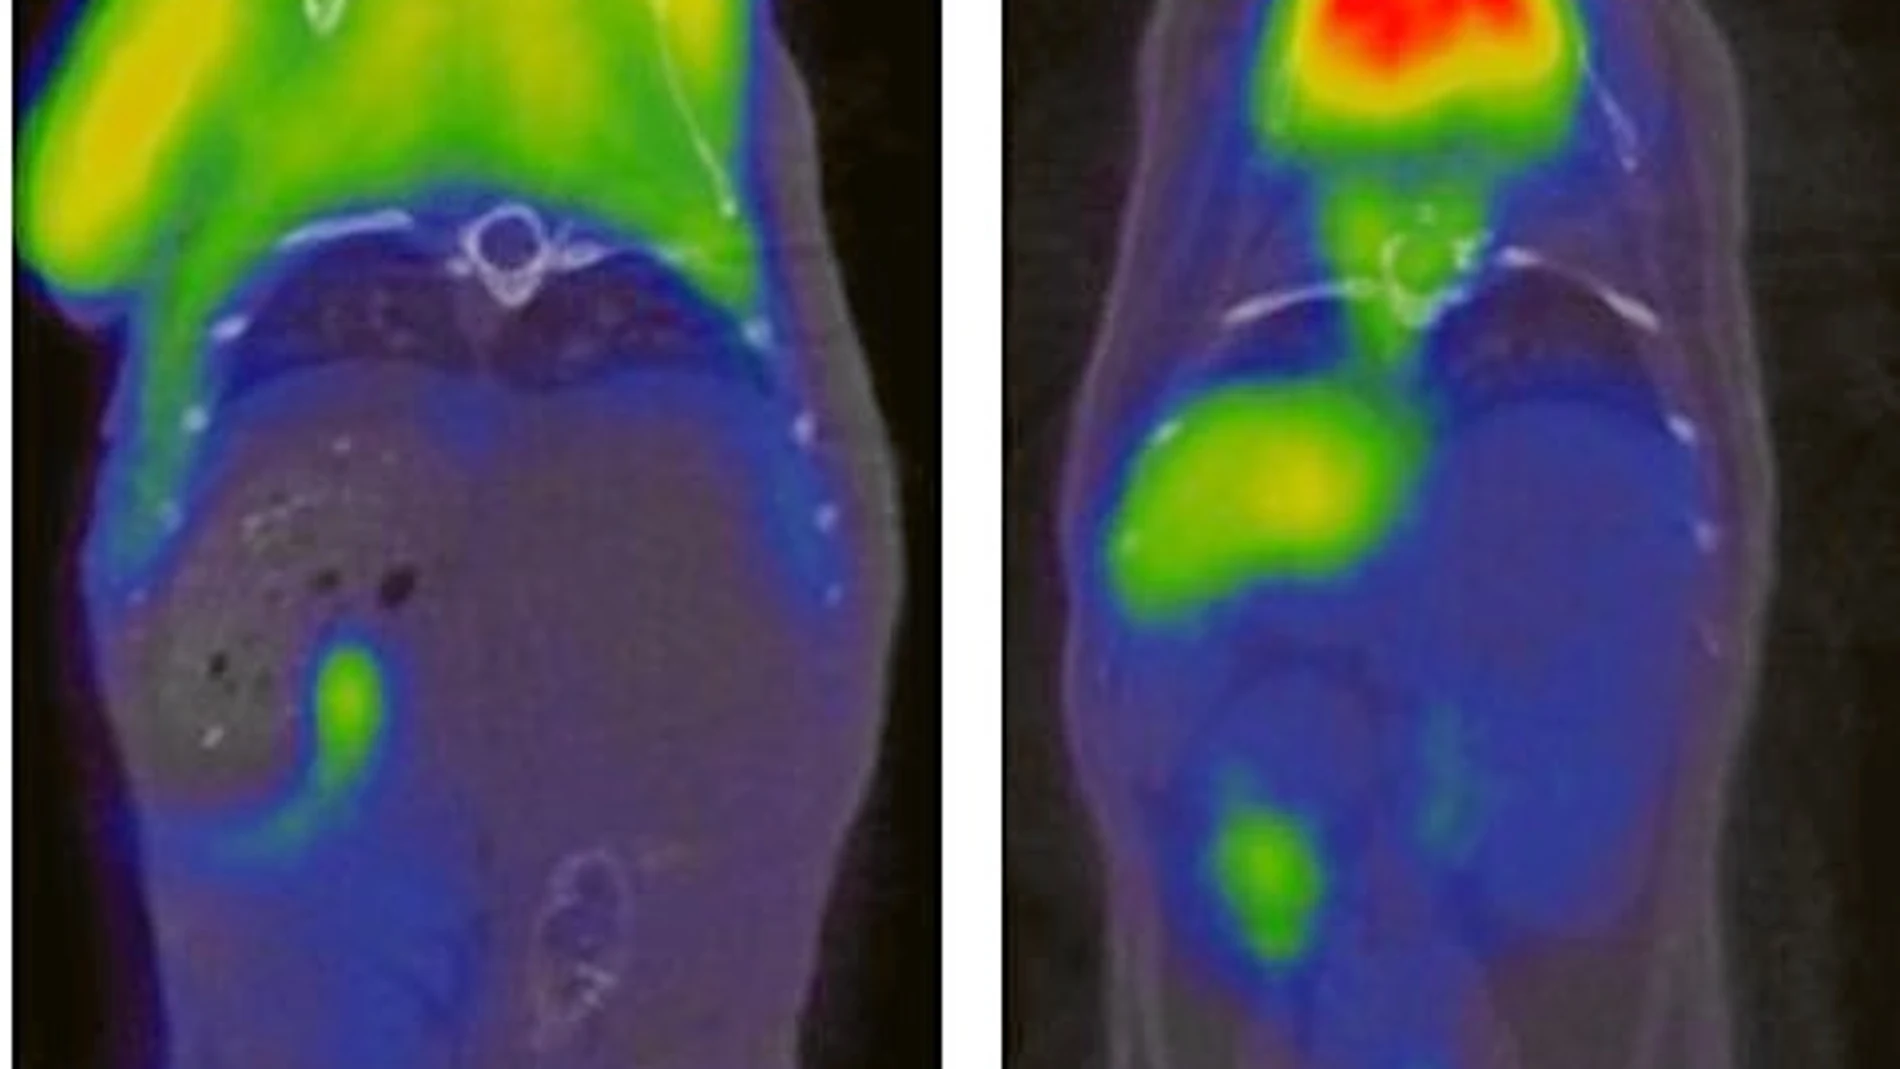

Los trabajos se han realizado sobre ratones de líneas conplásticas, es decir, cuentan con un genoma mitocondrial completo compartido con otras líneas cosanguíneas. Esto permite la comparación de la evolución de animales que puedan tener el mismo genoma nuclear y difieran en el mitocondrial. Por primera vez se ha estudiado el ciclo de vida completo de este tipo de ratones desde el punto de vista genético, proteómico, fisiológico y metabólico.

De ese modo se ha descubierto que la tipología de genes del ADN mitocondrial está relacionada con la forma en la que el organismo responde a los procesos de oxidación propios del envejecimiento, el modo en el que se comporta el metabolismo de la insulina, el desarrollo de la obesidad o la aparición de señales de envejecimiento como el acortamiento de los telómeros. Es decir, el paquete de fenómenos que indican que un ser vivo está envejeciendo se activa más o menos en virtud de la tipología de ADN mitocondrial que ese individuo porte en sus células.